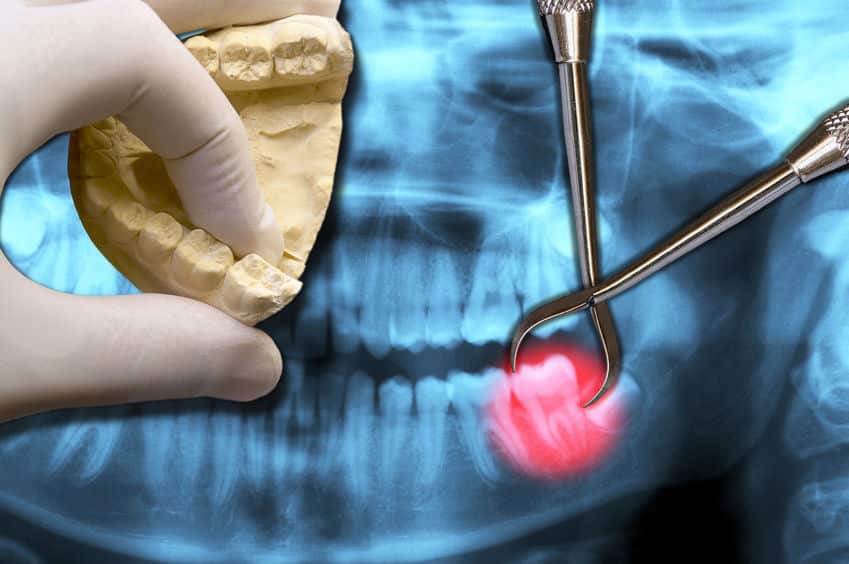

خلع الضرس هو عملية إزالة السّن من تجويفه الموجود في العظم، وهناك العديد من الأسباب التي تستدعي القيام بخلع الأسنان من أهمها كسور الأسنان وتسوسها، وقد كان خلع الأسنان قديماً من أهم الطرق المُتبعة لعلاج الأسنان، وهناك نوعان رئيسيان لخلع الأسنان ألا وهما:

الخلع البسيط والخلع الجراحي، وفي حالات الخلع البسيط يكون الضرس المُراد خلعه ظاهراً في الفم، ويتم فيه تحريك السّن ومن ثمّ خلعه، أمّا الخلع الجراحيّ فيكون أكثر تعقيداً حيث تكون الأسنان المُراد خلعها مكسورة تحت مستوى اللّثة، أو مطمورة وذات بزوغٍ غير مكتمل.

هناك العديد من الأسباب التي تستدعي خلع الأسنان، من أهم هذه الأسباب التهاب السّن وتكوّن خراجٍ فيه، كما أن خلع الأسنان يتم في الحالات التي تكون فيها أمراض اللثة قد أدّت لتحرّك الأسنان، ويتم الخلع أيضاً في حالات الأسنان المطمورة التي تسبب بعض المشاكل مثل أضراس العقل المطمورة، ومن الأسباب التي تستدعي خلع الأسنان أيضاً، ضربات الأسنان أو الحوادث، وتزاحم الأسنان.